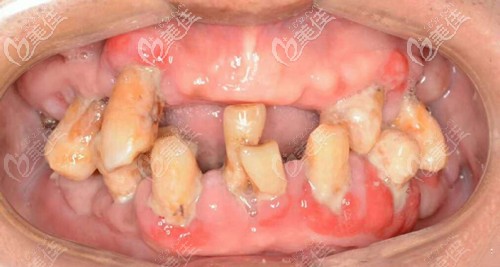

術(shù)前照片:

老年人沒有一口好牙可太受罪了,我姥爺就是活生生的例子,牙齒基本掉了挺多的,吃飯不容易、說話還漏風(fēng),我看著都替我爺難受。

做種植牙前牙齒缺失、牙齒松動、牙周病較厲害

邱醫(yī)生說我姥爺?shù)目谇恍l(wèi)生狀況不太好,牙周石比較厲害,牙齒缺失,雖然現(xiàn)在口內(nèi)還10顆牙齒,也開始出現(xiàn)了松動的跡象,陸續(xù)的牙齒都會脫落,沒有其他方案可以選擇了。

比較合適的方案就是做拔掉殘余的牙齒,上牙種植6顆、下牙種植6的全口即刻種植、即刻修復(fù)。可以避免植骨粉,還能當(dāng)天種牙后,就能戴牙冠,回家就能正常吃飯啊什么的。